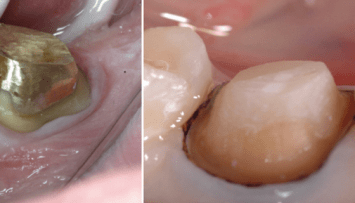

Die Endodontie hat in den vergangenen Jahren einen immensen Fortschritt erlebt. So können heute mit Zuhilfenahme moderner Geräte und Techniken auch Zähne erfolgreich erhalten werden, die noch vor geraumer Zeit als nicht erhaltungsfähig galten.